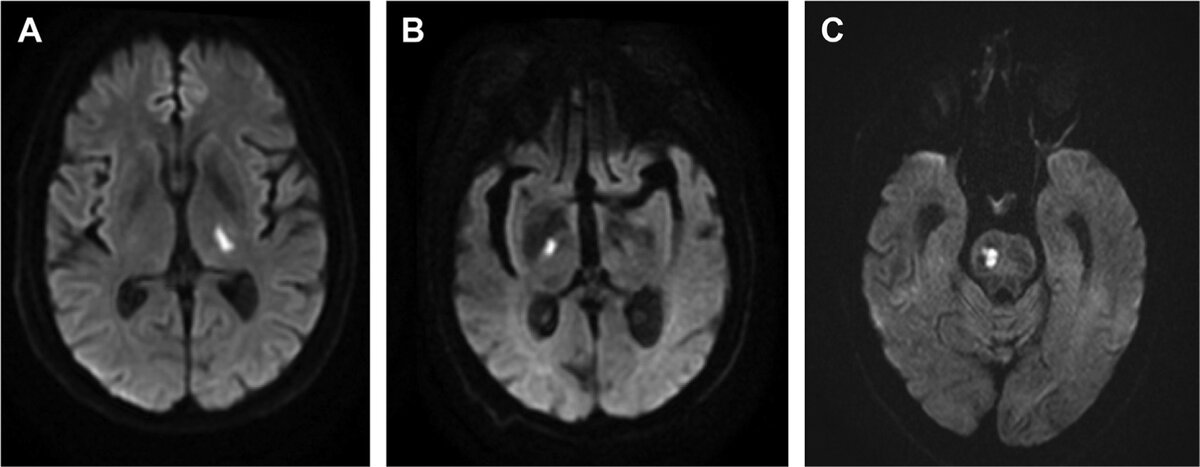

Инфаркты размером менее 20 мм в типичных для инфарктов мелких сосудов местах соответствуют лакунарным инфарктам. ( А ) Аксиальная диффузионно-взвешенная МРТ демонстрирует острый инфаркт левого таламуса у курильщика с гиперлипидемией. ( Б ) Аксиальная диффузионно-взвешенная МРТ демонстрирует острый инфаркт правой внутренней капсулы у пациента с множественными сосудистыми факторами риска. ( C ) Аксиальная диффузионно-взвешенная МРТ демонстрирует острый инфаркт правого моста у пациента с гиперлипидемией и гипертонией.